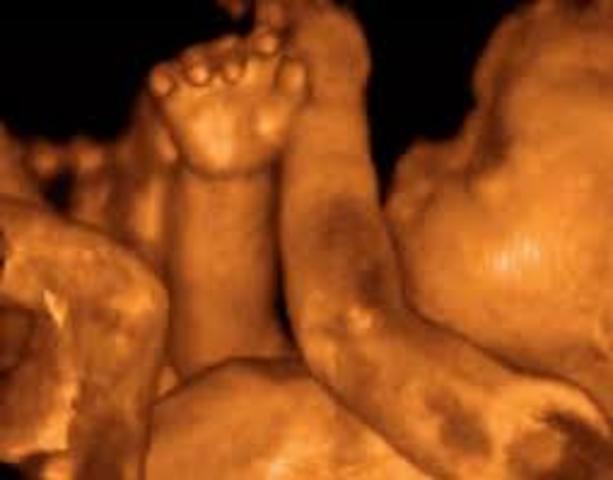

Es muy probable que tu bebé ya se haya acomodado y tenga la cabeza en tu pelvis preparado para salir en unas semanas más. Sentirás que te molestarán más sus movimientos porque está más grande y cuando se estire puede que veas su pequeño pie.